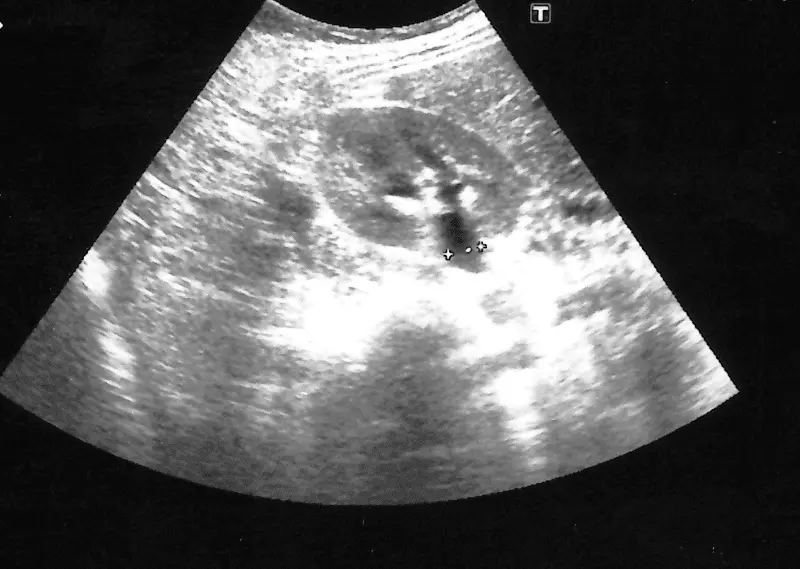

W powtórzonym badaniu USG, zaprezentowanym na rycinie 7, uwidoczniono złóg lub konglomerat drobnych złogów o wymiarach 8 x 3 mm w przypęcherzowym odcinku prawego moczowodu w odległości około 1 cm od pęcherza oraz powyżej niego widoczny poszerzony moczowód szerokości 6–8 mm. W kielichach środkowych nerki prawej uwidoczniono złóg wielkości 5 mm.

Ryc. 7. Obraz USG z a) widocznym złogiem/konglomeratem złogów w przypęcherzowym odcinku moczowodu i b) z poszerzeniem moczowodu powyżej złogu